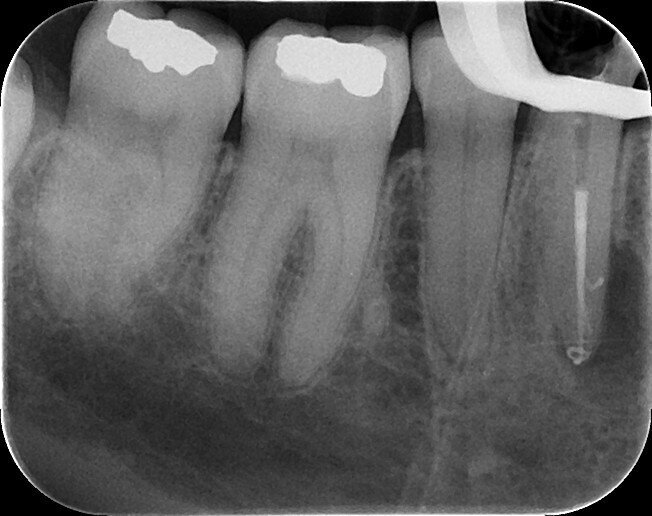

Fig. 5: VDW.ROTATE 15.04 and 20.05 files inserted into the root canals for the working length radiograph.

Fig. 6: Working length radiograph.

A radiograph to confirm the final working lengths was carried out with an endodontic ring holder and the VDW. ROTATE 15.04 and 20.05 files (Figs. 5 & 6). The last instrument at the apex was the 25.04 file owing to its flexibility and reduced core (compared with the 25.06 file) using the same strategies as in the previous steps. Final rinses with EDTA solution and sodium hypochlorite were followed by activation of the solution with a pre-bent EDDY tip (VDW, Fig. 7) for 20 seconds. The canals were then dried and filled with AH Plus (Dentsply Sirona) and two gutta-percha cones matching the VDW.ROTATE instruments (VDW) and made of a more heat-conductive gutta-percha with a lower melting temperature using the continuous wave technique up to the bifurcation. A radiograph was taken (Fig. 8) to check the root canal fillings and then a fibre post and core build-up were carried out. The final radiograph showed good filling of the root canals with small extrusions of the sealer through the buccal foramen and a lateral canal (Fig. 9). The patient was referred to her dentist for permanent restoration of the tooth. Six months of follow-up was planned in order to control the outcome of the treatment.